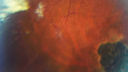

Microaneursyms and Macular Edema Not Diabetic373 views85 year old man has been tested about 2-3 times and is always negative for diabetesDec 20, 2018

|